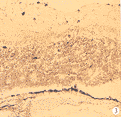

2.2 组织学检查结果:移植前胚胎期2周供体视网膜,仅见单一多细胞层,富含细胞核,尚未见内外颗粒层的分化。移植术后1周移植区受体视网膜神经上皮与色素上皮分离,被移入的视网膜细胞失去原来正常的片段状排列,大部分呈花环状排列,花环由中央空腔及周围向心排列的细胞团组成,近中央处细胞核轻度椭圆状,深染,花环边周核圆,淡染(图1)。移植后2~3周:移植区可见两种细胞的继续分化分层,近中央区胞浆红染,形态类似外节,指向中央空腔,但较短。个别地方未形成花环,呈条形排列,可见内外核层分化,相当外节部分指向受体色素上皮层,也有朝向受体内界膜方向(图2)。4周移植物细胞排列仍大部分呈花环状,内外核层分化明显,在受体及植片之间可见核固缩细胞。实验组和对照组术后1~4周未见明显脉络膜血管扩张、充血,无淋巴细胞及单核巨噬细胞浸润。

图2 片层样生长

Fig.2 Film growing